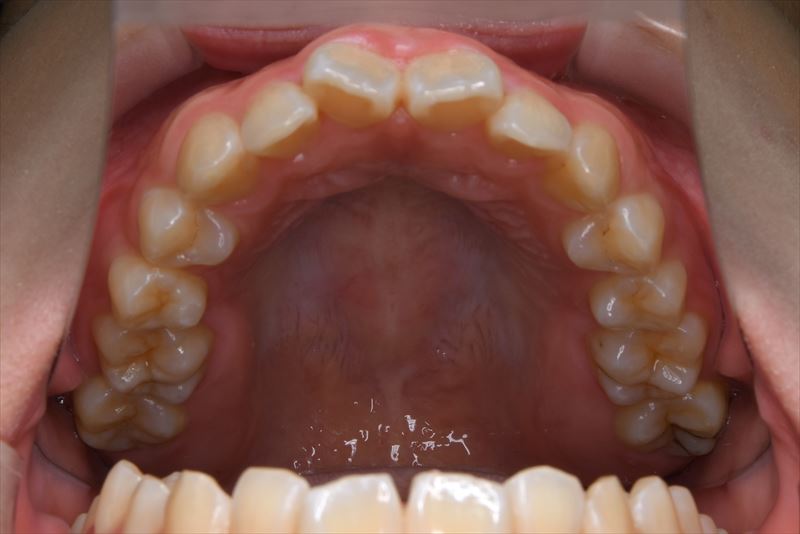

治療後

- 抜歯/非抜歯部位

- 上顎両側4番、下顎右側5番、下顎左側4番抜歯

- 口唇の突出を気にされて来院いたしました。Eラインより口唇の突出、オトガイ部の緊張を認めました。アンカースクリューを用いて前歯の牽引を行うことによって良好な側貌となりました。治療途中で遠方に引っ越されたため来院が困難となり治療期間が延びてしまいましたが、患者様のご協力もあり無事に治療を終えることができました。